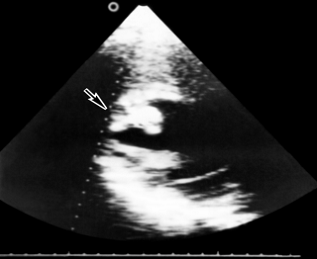

Рис. 24а). Эхокардиограмма больного с экссудативным перикардитом: двухмерная эхокардиограмма в проекции длинной оси (эхонегативные полости представлены темными, а эхопозитивные структуры - светлыми полями); хорошо определяется эхонегативное пространство (указано стрелками), за задней стенкой левого желудочка - полость перикарда, заполненная выпотом

Рис. 22. Двухмерная эхокардиограмма (в проекции длинной оси сердца) больного с миксомой левого предсердия: стрелкой указано овальной формы эхопозитивное образование, расположенное в левом предсердии

Рис. 23а). Двухмерная эхокардиограмма больного с тромбом в левом желудочке сердца: на двухмерной эхокардиограмме в полости левого желудочка (темное поле) определяется интимно связанное со стенкой и выбухающее в полость плотное эхопозитивное образование (указано стрелкой), которое в одномерном изображении представляется слоистым, заполняющим почти всю полость левого желудочка